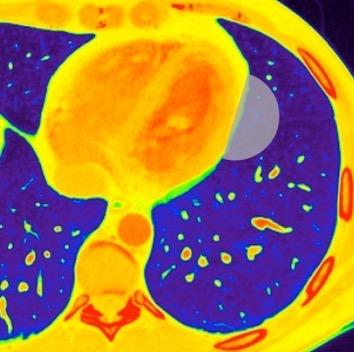

Edad: 40-50 años

3% segregan catecolaminas.

(En el área Paravertebral +/-50%.)

Intenso realce con el contraste.

32 años .Preeclampsia a los 19. Hipertensión no controlada. Masa paravertebral sólida que se realza intensamente con afectación ósea.

Yue Y t al. Asymptomatic left posterior mediastinal functional Paraganglioma. A case report. Medicine . 2019